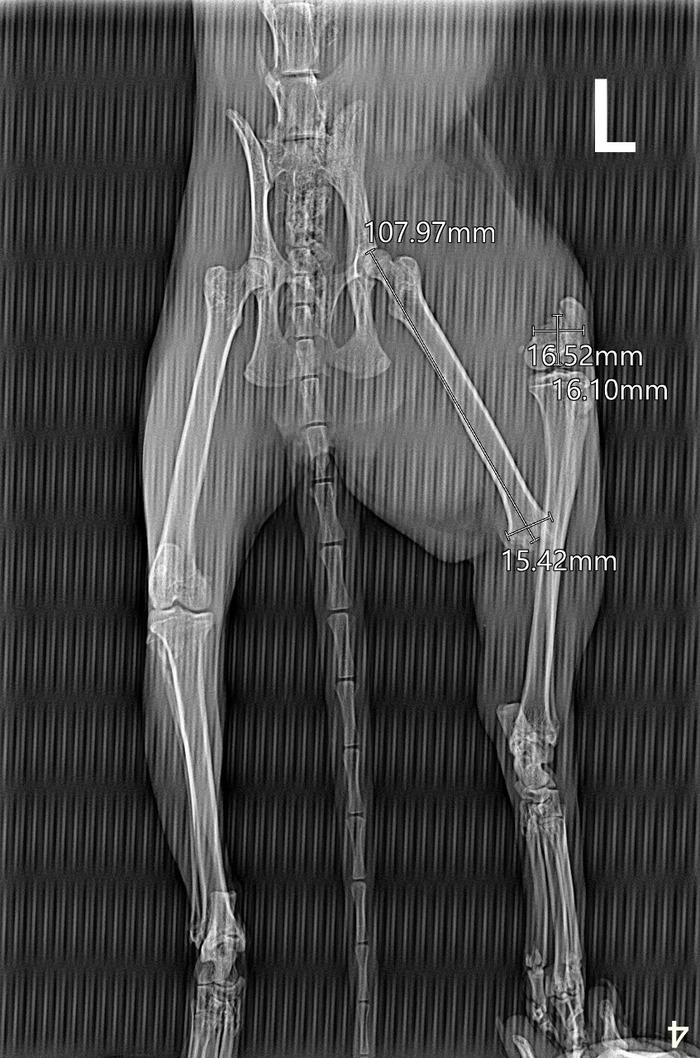

Но тем не менее у данной породы есть генетические проблемы с позвоночником и задними конечностями. Как сообщил ветеринар:

"Дисплазия ТБС может быть, действительно, без рентгена это не от диагностировать, также возможны и другие патологии пояснично-крестцового отдела позвоночника вызывающие сходную симптоматику"

К сожалению рентген ему сейчас не сделать, т.к. он не набрал свой вес, а с истощением нельзя давать ему седативные (а без них рентген не сделать).

Но это не срочная процедура, поэтому ждет.